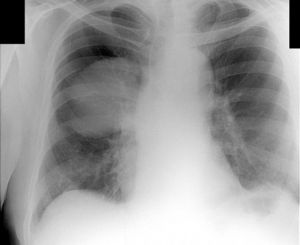

На снимке или другом виде изображения врач видит черно-белую картинку – человеческие легкие. Для неподготовленного человека это ни о чем не скажет, специалист же сможет выявить многие недуги, даже начинающийся бронхит.

Уплотнения выделяются изменением окраса тканей в определенном месте. Исходя из интенсивности цвета, размера, месторасположения и других данных ставят предварительный диагноз.

Именно поэтому обычно рентгенолог не пишет, что присутствует подозрение на воспаление легких, туберкулез. Окончательный диагноз здесь даст исследование мокроты, а не картинка.